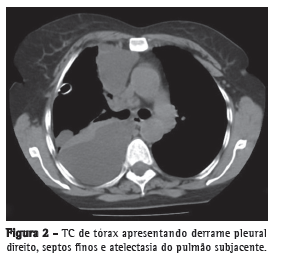

A radiografia de tórax demonstrou significativo derrame pleural do lado direito (Figura 1), e TC de tórax revelou derrame pleural à direita, septos finos, e atelectasia do pulmão subjacente (Figura 2). Os níveis séricos de uréia e creatinina foram 132 mg/dL e 3,9 mg/dL, respectivamente. Visto que o desconforto respiratório desenvolveu-se subitamente e logo após a nefrolitotomia percutânea, houve a suspeita de urinotórax. O diagnóstico foi confirmado após toracocentese, que produziu aproximadamente 1.100 mL de líquido pleural, com uma relação entre o conteúdo de creatinina no líquido pleural e aquela no soro foi de 1,78 (normal, < 1). Um dreno de 28 Fr foi inserido no quinto espaço intercostal direito a fim de drenar o derrame.